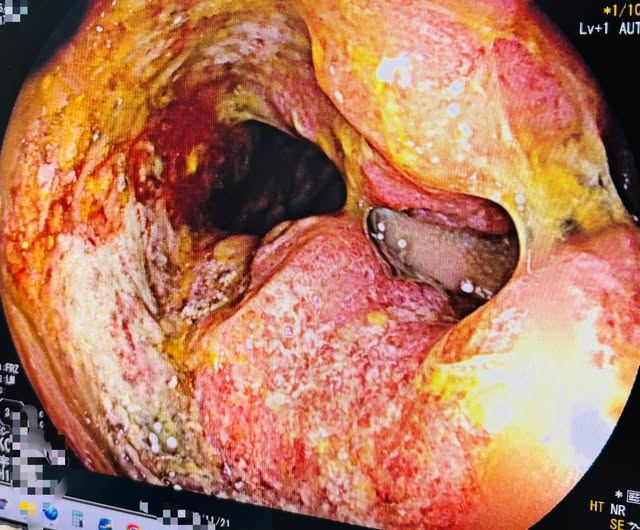

一名中年男子長達半年血便未予理會,直到排便不順才就醫,被診斷出直腸腫瘤,且已造成腸道阻塞。(圖/陳英傑醫師授權提供)

農曆新年將至,正當家家戶戶忙著採買年貨、沉浸在喜氣氛圍時,診間內卻上演了一幕令人心碎又動容的醫病對話。一名中年男子因長達半年的血便未予理會,直到排便不順才就醫,竟被診斷出直腸腫瘤且已造成腸道阻塞。面對沉重的報告,病患一句豁達的「老實說沒關係」,反而給了糾結不已的醫師莫大的勇氣。

陳英傑醫師指出,最初雖然先開立藥物觀察,但回診後發現症狀毫無改善。憑藉專業直覺,他主動安排了大腸鏡檢查,不料結果顯示為直腸腫瘤,且腫瘤體積已大到引發腸道阻塞,情況不容樂觀。